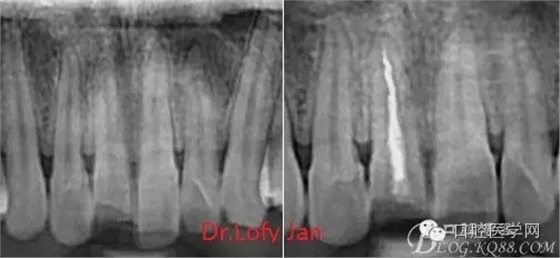

曲面斷層片在未試尖根管治療中的病例整理

前言:自己做的一些曲面斷層片在未試尖根管治療中的病例整理,發(fā)現(xiàn)問題很多包括自身的,技術(shù)的,還有設備的問題,予以總結(jié)整理并期待進一步提高。

根管治療術(shù)是牙體牙髓疾病治療中最復雜和最關(guān)鍵的治療項目。根管充填材料抵達根尖、并能嚴密堵塞根尖孔,是確保根管治療效果的關(guān)鍵指標。為了保證根管充填到位,醫(yī)生需要在術(shù)前照牙片以了解牙根根管的數(shù)量、彎曲程度和長度,在術(shù)中有時需要插針照牙片來精確測量根管長度,術(shù)后必須照牙片以確定是否根管充填到位,如果欠填或超填,就需要重新充填、重新照牙片確認,直到根管充填到位。所以,在患者接受根管治療時有時會反復照牙片。

病例分析:曲面斷層片在x線輔助診斷與檢查中目前大多數(shù)文獻和著作都建議只能作為初診拍片檢查手段,不能作為終末疾病的確診與手術(shù)療效的評價指標,臨床大部分中小型門診都因為設備不齊全導致信息偏差很大。